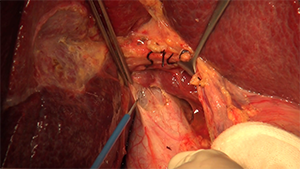

腹腔镜肝S4段+右前腹侧段切除术

作者:吴柯 | 作者单位:陆军军医大学新桥医院

发布时间:2020-09-03 21:59:28